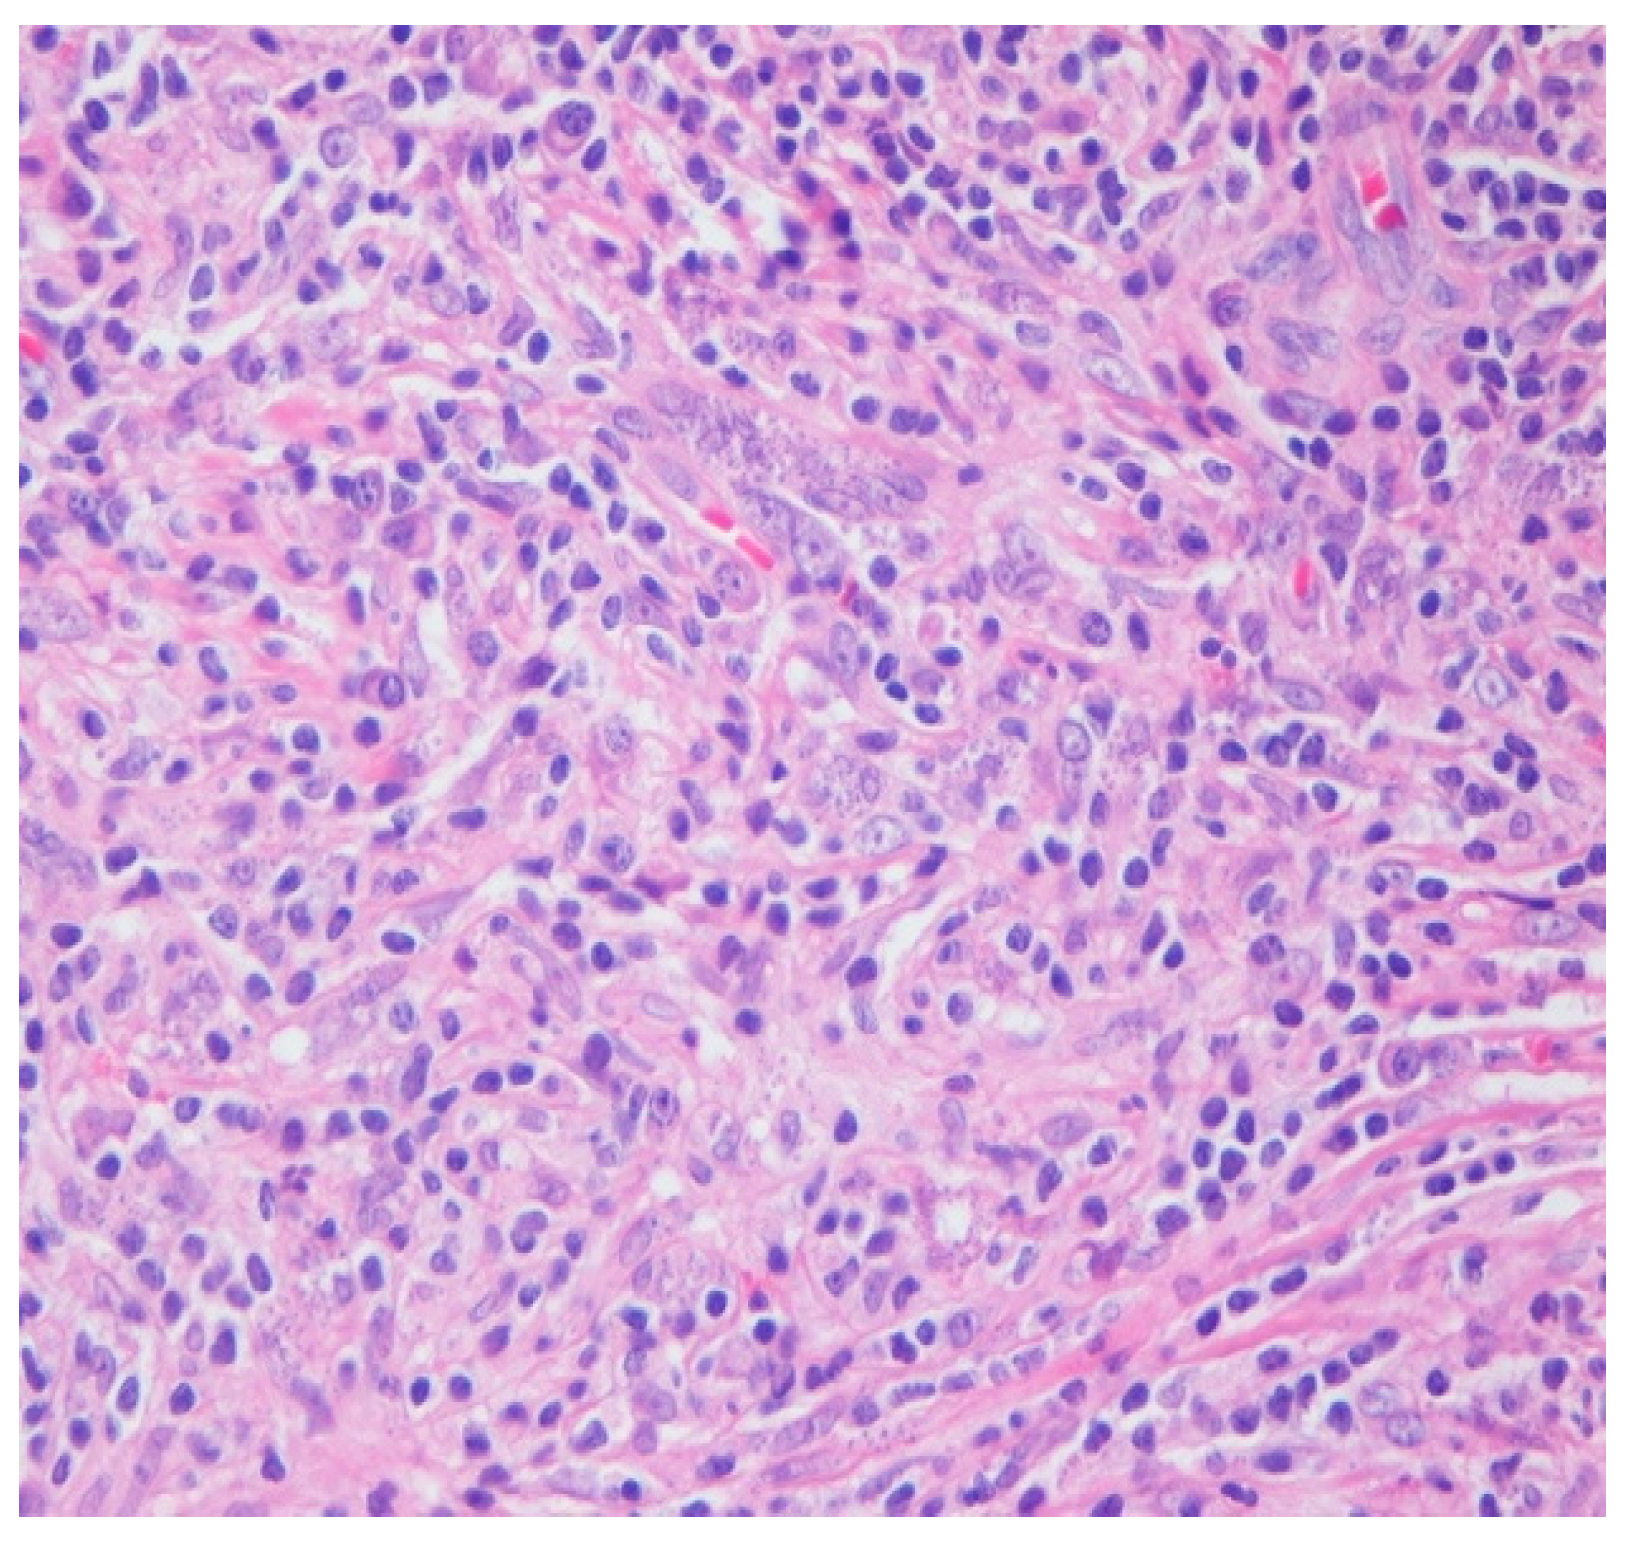

Intraoperatively, the nasal mucosa appeared friable, and the cartilaginous septum was fragmented and necrotic. Tissue samples were collected for histological examination. Histopathological evaluation of the biopsied cartilage and mucosa revealed squamous epithelial hyperplasia and surface erosion with associated crusting. The lamina propria was markedly expanded and infiltrated by a dense, diffuse inflammatory infiltrate consisting of lymphocytes, histiocytes, plasma cells, and occasional multinucleated giant cells. Notably, numerous intracellular amastigotes, consistent with Leishmania spp., were identified within histiocytes (Figure 2 and Figure 3). These findings were highly suggestive of mucosal leishmaniasis in the context of chronic nasal inflammation. Laboratory tests revealed normal blood counts and renal function, with minimal inflammatory marker elevation. Serologic testing was positive for rK39, supporting a diagnosis of active Leishmania infection, although PCR testing was negative, and CPA was indeterminate.

Figure 3. HE 40×. Admixed histocytes, lymphocytes, and plasma cells, as well as intracellular organisms with round, basophilic structures and rod-like kinetoplasts scattered haphazardly and filling the histocytes (amastigotes).